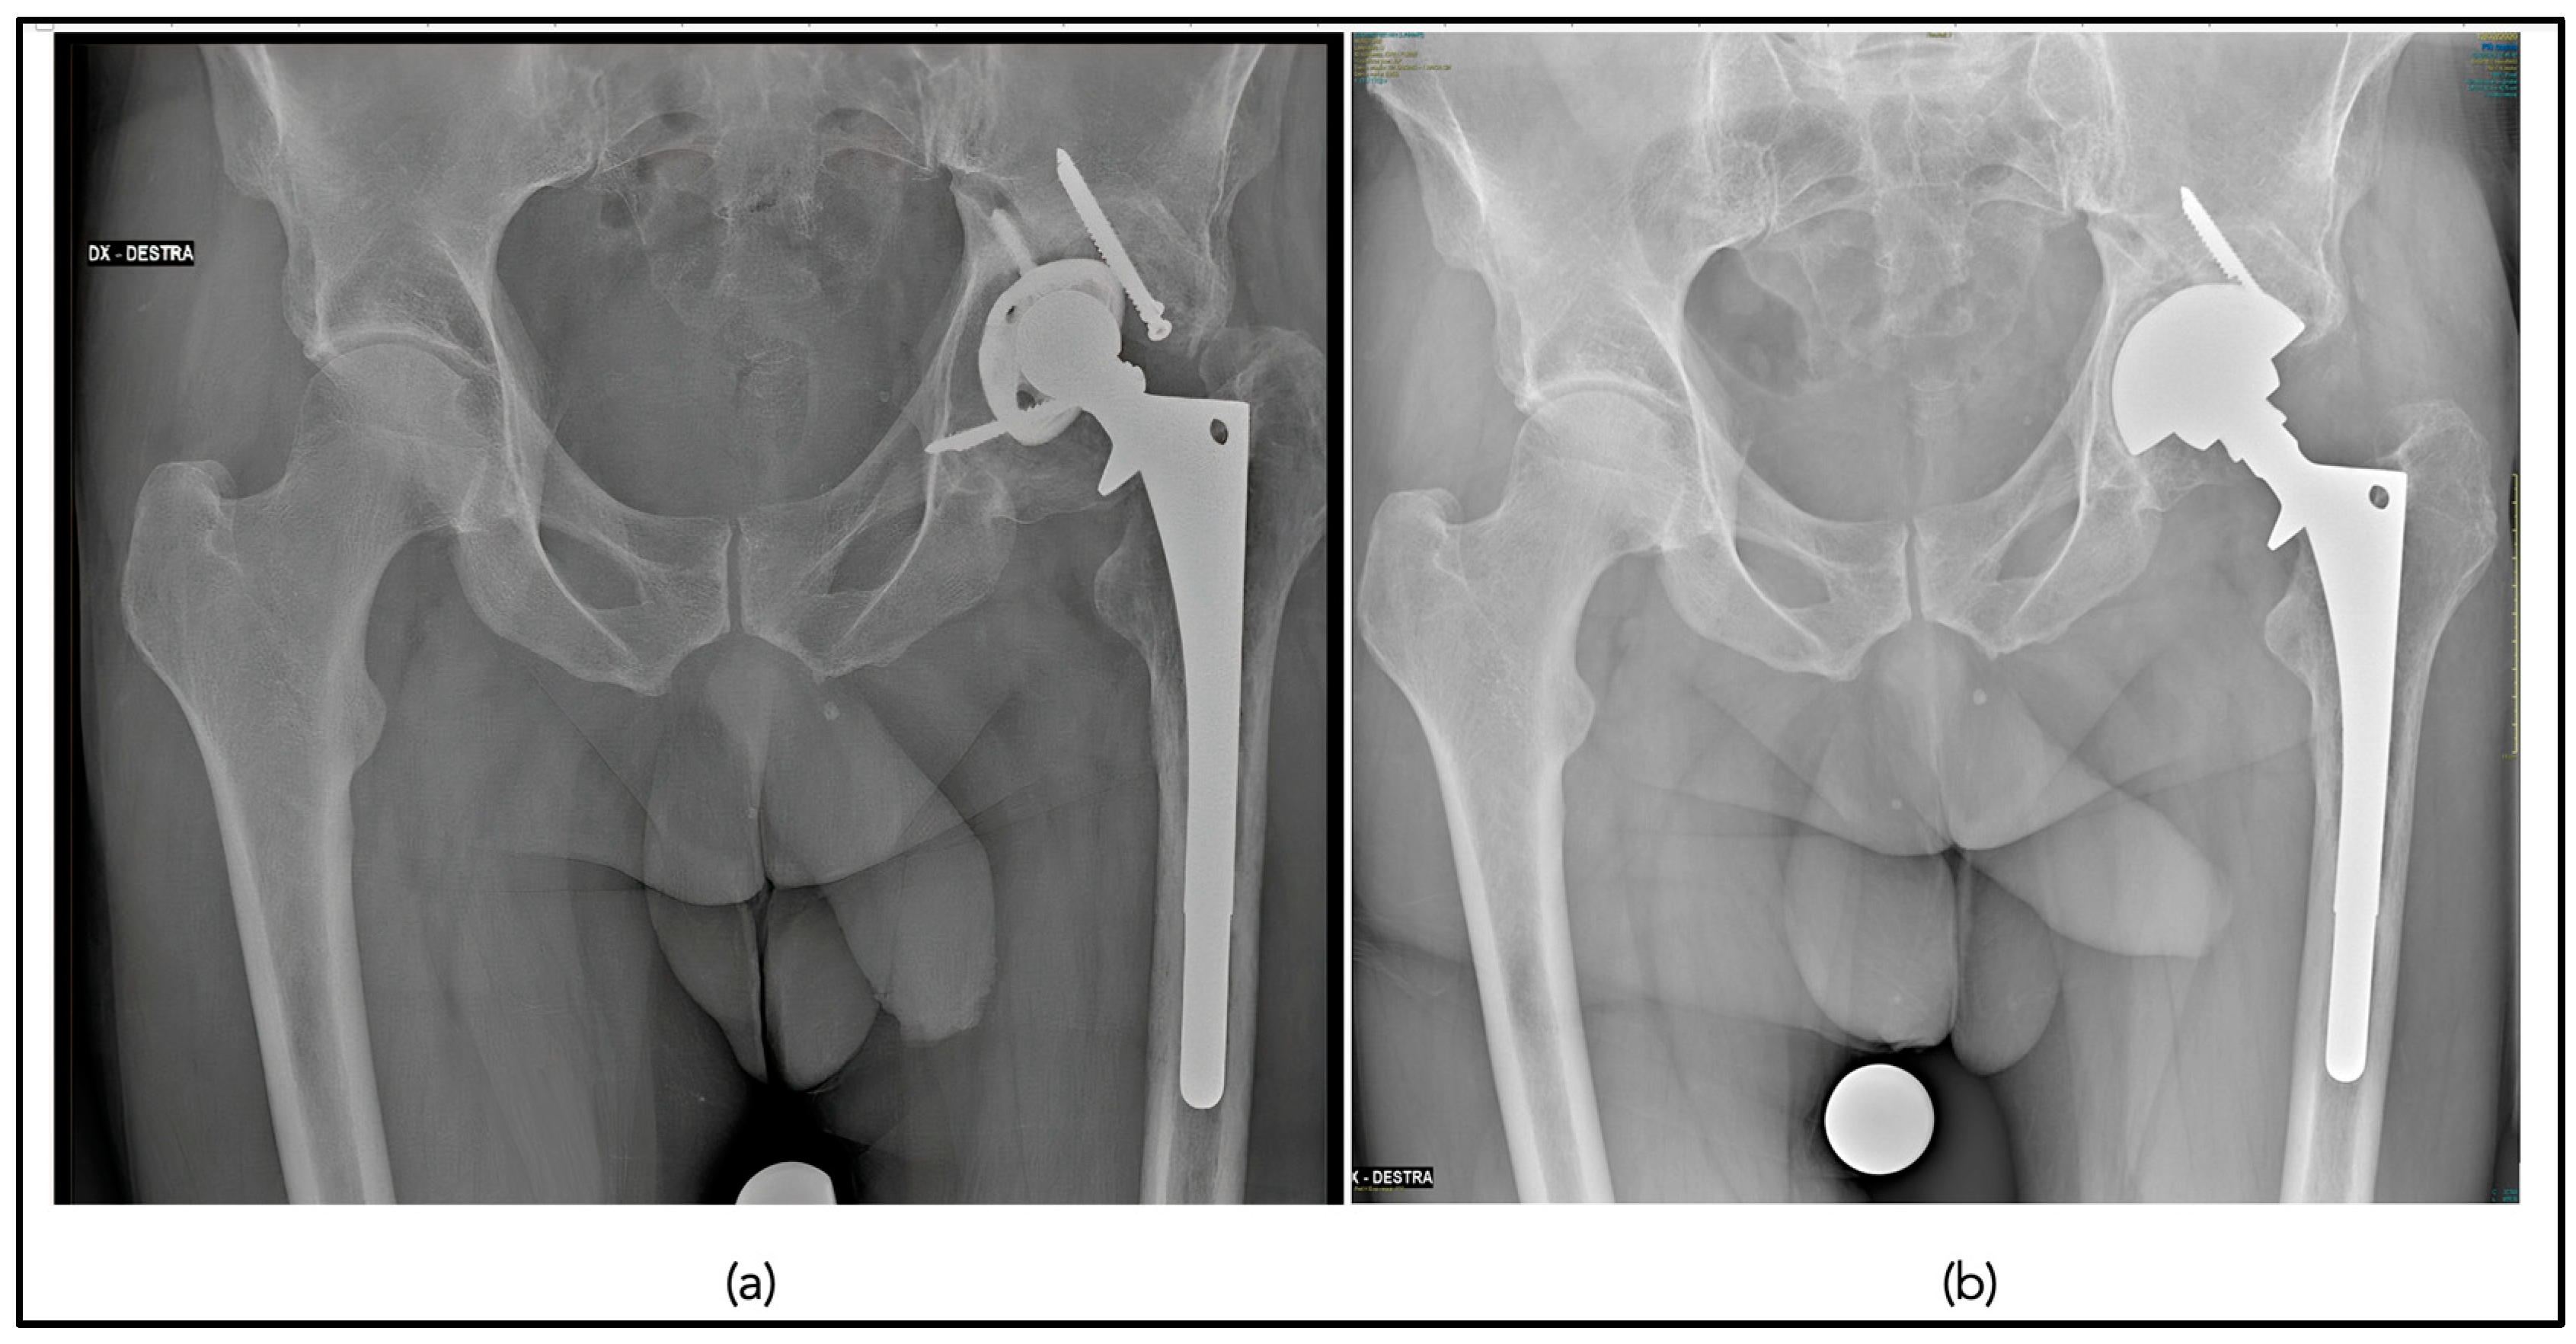

No cup or stem components showed progressive radiolucent lines or osteolysis at the last follow-up (Figure 4).

No cup or stem components showed progressive radiolucent lines or osteolysis at the last follow-up, Image 3. No component migration occurred. Cups showed good signs of radiographic osseointegration (>3 Moore criteria for bony ingrowth) in 13 cases (40.6%). Stems showed good signs of bony ingrowth in 17 hips (53.1 %) with a mean Engh criteria of 11.6 ± 7.5. The mean post-operative femoral offset (48.8 mm ± 10.33) was larger than the contralateral side (45 mm ± 7) (p = 0.02). The post-operative acetabular offset was 38 mm ±6.4 compared to 39.3 mm ± 7.2 of the contralateral side (p = 0.08). The mean LLD was 8.7 mm ± 8.1. The mean post-operative vertical offset was 23 mm ± 4.6 compared to 22.79 ±4.7 of the contralateral side (p = 0.06). The post-operative acetabular cup inclination was 42.7° ± 8.2 compared to 42.4° ± 7.1 (p = 0.07).

Figure 4. Pre-operative anteroposterior pelvic radiograph demonstrating cup mobilization and polyethylene liner wear (a); post-operative anteroposterior pelvic radiograph at 5 years following stem retention use of the Bioball head–neck adaptor and revision of the acetabular component (b).